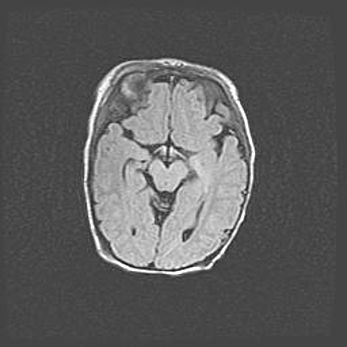

Наружная гидроцефалия с возможной атрофией височных областей.

Возраст: 28 дней

Вес: 3670 г

Пол: мужской

Окружность головы: 38 см

Срок гестации: 40 недель

Гидроцефалия головного мозга у новорожденных – это заболевание, которое характеризуется скоплением избыточного количества спинномозговой жидкости в желудочковой системе головного мозга в результате затруднения её перемещения от места выработки к месту поглощения в кровеносную систему или вследствие нарушения абсорбции. При открытой наружной форме гидроцефалии у новорожденных расширяются и переполняются субарахноидные пространства.

При нормотензивных  формах,  которые,  как  правило,  являются  следствием  перенесенных ишемических  повреждений  паренхимы  мозга,  возможно  сочетание микроцефалии  с нормотензивной гидроцефалией. В основе данных изменений лежит атрофия больших полушарий с преимущественной  локализацией  в  лобно-височных  областях.